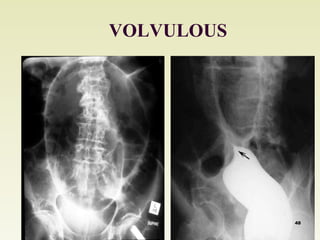

VOLVULOUS

2. Other causes of intestinal obstruction

b. Volvulus